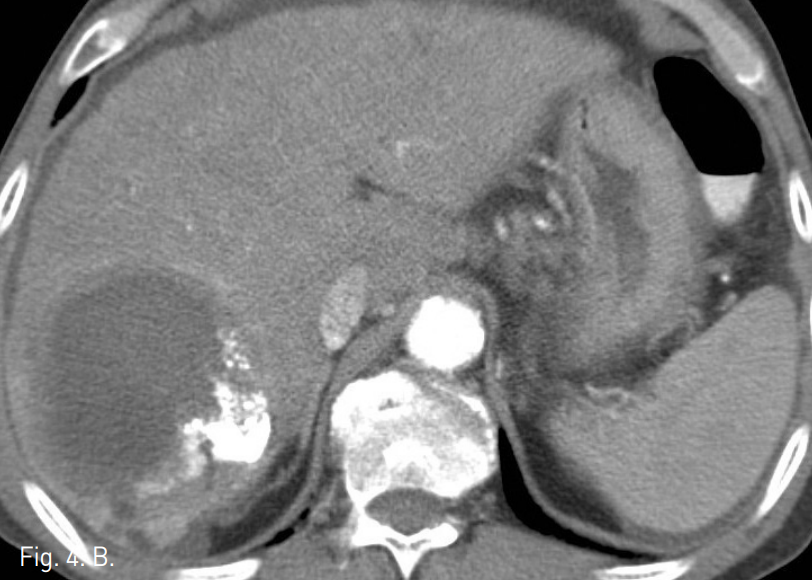

외래에서 시행한 복부 CT에서 간 우엽에 간동맥과 연결성을 보이는 2.5cm 크기의 가성 동맥류가 관찰되며 주위에 9cm 크기의 혈종이 있음. 간경변증을 보이고 있으나 간내에 간세포암종을 시사할만한 비정상적으로 조영증강되는 종괴의 소견은 관찰되지 않음(Fig. 1). 복부 MR에서 혈종의 뒤 안쪽으로 3.5cm 크기의 간세포암종으로 생각되는 병변이 관찰됨(Fig. 2).

Fig. 1

A, B. Axial (A) and coronal (B) CTimages of arterial phasereveal high density pseudoaneurysm and surrounded low density hematoma in the right lobe of the liver.

시술 2개월 후 시행한 조영증강 복부CT에서 우 간동맥에 의한 간내 가성동맥류는 보이지 않았고, 혈종은 약간 작아진 상태로 여전히 남아있었다(Fig. 4A). 간내종양은 lipiodol이 침착된 상태로 재발의 소견은 없었다(Fig. 4B).

Fig. 4

A, B. Two months after coil and chemoembolization, contrast-enhanced CT images show still remained hematoma and lipiodol Haden lesion without pseudoaneurysm.